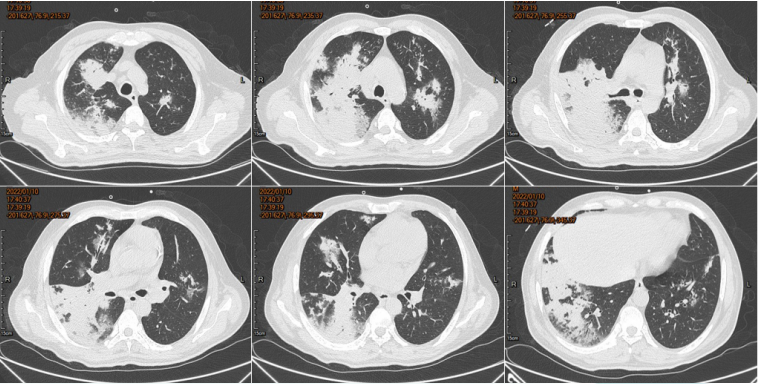

患者胸部CT动态变化如图17所示。临床结局:好转出院。

图片

17  病例3胸部CT动态变化